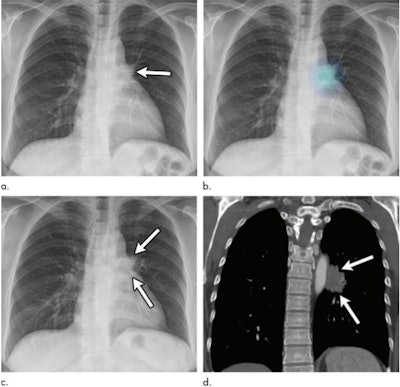

An artificial intelligence (AI) algorithm can help reduce the number of missed lung cancers on chest x-ray, according to a study published July 21 in Radiology. The study results point to AI as an effective way to address the challenging task of spotting subtle suspicious lung lesions.

"Our findings suggest that a deep learning-based automatic detection algorithm (DLAD) may contribute to a reduction in the number of lung cancers overlooked on chest radiographs by improving observer performance," wrote a team led by Dr. Sowon Jang of Seoul National University Bundang Hospital in South Korea.

The authors found that the AI algorithm improved readers' ability to detect cancers that had been missed on chest x-ray. They also found that in the healthy cohort, there was no difference between the rate of chest CT recommendations when the algorithm was used and when it wasn't.